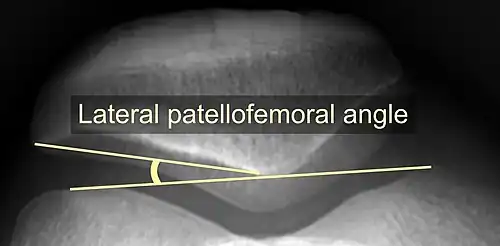

On X-ray, with skyline projections, dislocations are readily diagnosed. In borderline cases of subluxation, the following measurements can be helpful:

- The lateral patellofemoral angle, formed by:[16]

- A line connecting the most anterior points of the medial and lateral facets of the trochlea.

- A tangent to the lateral facet of the patella.

- With the knee in 20° flexed, this angle should normally open laterally.[16]

- The patellofemoral index is the ratio between the thickness of the medial joint space and the lateral joint space (L). With the knee 20° flexed, it should measure 1.6 or less.[16]